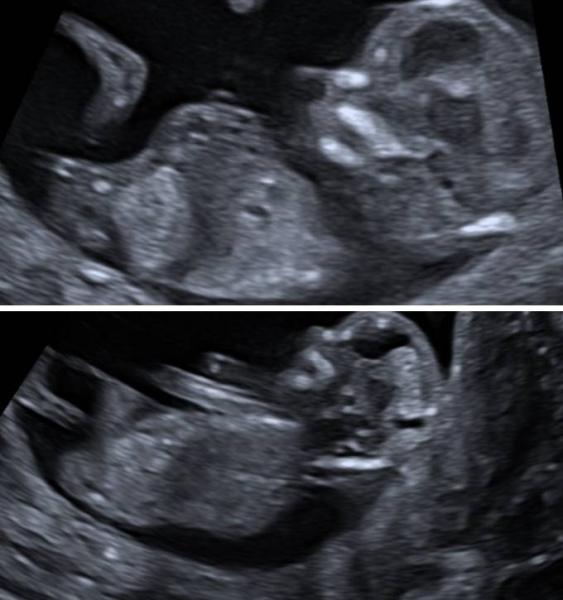

Wow, Wahnsinn, einfach nur der absolute Hammer .. Wir waren heute beim ersttrimesterscreening, alles ist super und genau wie es sein soll, die Chance auf eine Trisomie und eine erneute Präklampsie ist sehr unwahrscheinlich . Ich hab eine Vorderwandplazenta, merke die Bewegungen aber trotzdem schon (gut ist auch meine 3. Ss) Und das Highlight, er gab uns eine vorsichtige Tendenz, mit dem Hinweis, das er es eigentlich nicht sagen darf, aber ich habe ihn eine explizite Frage gestellt im Bezug auf Präklampsie und dem Geschlecht.. Dann haben wir noch Fotos bekommen und 2 Menschen, die sich auskennen, bestätigten seine Vermutung anhand der Bilder. So wie es aussieht sind wir im Team Rosa Ich hoffe bei euch ist alles gut und es geht euch gut, meine große hatte im Test aus der Schule noch 30 von 30 Punkten. Heute ist ein soo toller Tag.

Bild zu Ersttrimester screening.. und (vorsichtiges) Outing - Forum für April - Mamis